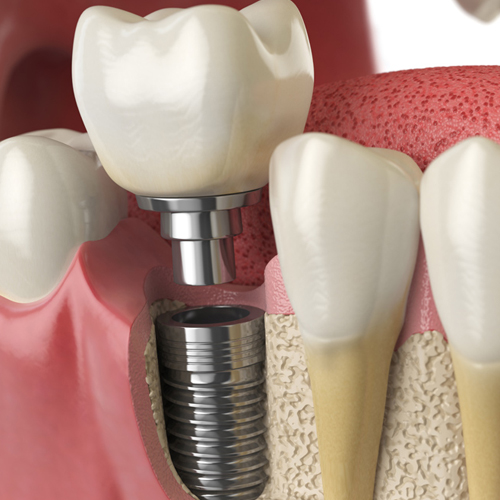

¿Qué son las coronas y puentes?

Las coronas y la mayoría de los puentes son prótesis que se colocan de manera fija. A diferencia de las prótesis removibles, que se pueden remover y limpiar diariamente, las coronas y los puentes fijos se cementan sobre los dientes o implantes existentes, y sólo un dentista puede extraerlos.

Prevención y control de la inflamación en pacientes con implantes dentales

La inflamación de los tejidos que rodean los implantes dentales constituye todo un desafío para dentistas y pacientes. A continuación, le decimos cómo las y los dentistas pueden ayudar a prevenir y controlar la enfermedad periimplantaria.